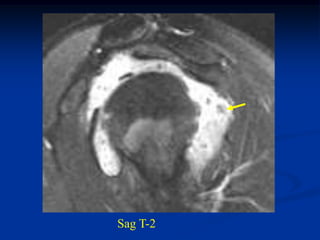

Case #1203.1   Pleomorphic liposarcoma      Axial CT scan

65 year male with recent onset buttock tumor mass in area of previous

resected large benign lipoma 6 years ago

Sag CT scan   Cor CT

Axial T-1     T-2

fluid

tumor

Gad

Sag T-2   Surgical specimen

Case #1203.1 Pleomorphic liposarcoma Axial CT scan 65 year male with recent onset buttock tumor mass in area of previous resected large benign lipoma 6 years ago

Axial T-1 T-2 fluid tumor Gad